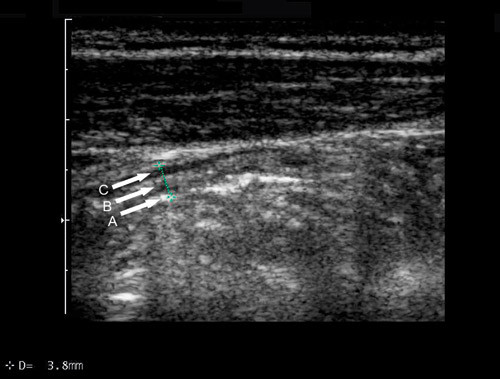

Med høyfrekvent ultrasonografi ses vanligvis fem lag i en normal tarmvegg (6, 7) enten man vurderer veggen fra serosa (transdusernære tarmvegg) eller fra mucosasiden (dorsale, transduserfjerne tarmvegg) (fig 1). Hvis det ses færre eller flere enn fem vegglag, kan dette indikere sykdom. For å undersøke om et tarmavsnitt er patologisk eller ikke, måles blant annet tarmveggens tykkelse. Lagdelingen i tarmveggen gjør at det oppstår overgangsekko når ultralydbølgene passerer fra et vegglag til et annet. Tykkelsen av tarmveggen måles oftest av den ventrale, transdusernære tarmveggen og vil da inkludere lagene 2 – 4, siden lag 1 i dette tilfellet er overgangsekkoet mellom lumen og mucosa. Overgangsekkoet mellom serosa og muscularis propria vil dessuten dekke en liten del av muscularis propria og således føre til at ventralsiden fremstår noe tynnere enn dorsalsiden med ultralyd. Siden dorsalsiden ofte er vanskelig å fremstille, velger man imidlertid ventralsiden som utgangspunkt for målingene.

I ileum anses veggen som patologisk fortykket dersom den måler mer enn 3 mm (8, 9). I tykktarmen varierer verdiene mellom normal og fortykket vegg fra 2,0 mm til 3,5 mm med økende tykkelse jo lengre distalt man kommer. Blodkar i tarmveggen er vanligvis så små at de ikke kan ses i B-mode ved transabdominal undersøkelse, men ved hjelp av fargedoppler kan blodstrøm fremstilles i disse karene (10). Ved bruk av høyfrekvente lydhoder må innstillingen justeres slik at lave blodstrømshastigheter kan oppdages. Veggfilteret må settes lavt, og hastighetsskalaen bør ligge rundt 2 – 8 cm per sekund. Grunnet bevegelsesartefakter bør pasienten holde pusten under dopplerundersøkelsen.